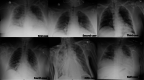

Coronavirus disease 2019 (COVID-19), caused by severe acute respiratory syndrome coronavirus 2 (SARS-CoV-2) is a global health emergency, in which its effective treatment and prevention remain obscured. Hyperpyrexia is an elevation of body temperature above 106.7°F (41.5°C) due to an abnormally increased hypothalamic-thermoregulatory set. The pathophysiology, impact, and outcomes of hyperpyrexia in patients with COVID-19 have not yet been studied. Herein, we present clinical features and outcomes of six patients with COVID-19 who had developed hyperpyrexia during hospitalization. All patients expired shortly after the onset of hyperpyrexia. Hyperpyrexia seems to adversely impact the outcomes and mortality in patients with COVID-19. The underlying mechanisms of developing hyperpyrexia in COVID-19 are mysterious. We propose it may be caused by SARS-CoV-2-related brain injury, exuberant immune response, and thrombus formation. More research is needed to verify our results. Understanding the association between hyperpyrexia and SARS-CoV-2 will help to elucidate the COVID-19 pathogenesis, which is mandatory for developing effective treatment strategies.

Figures